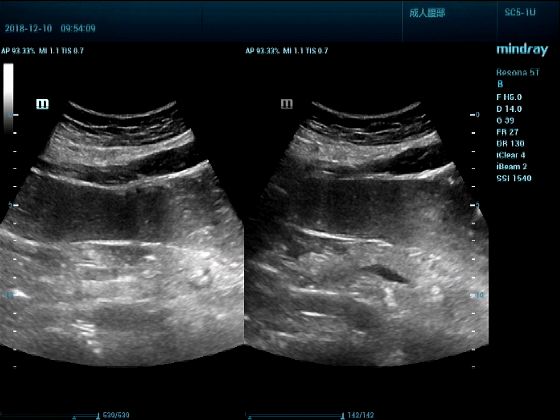

病例一:女,53岁,胃部不适一周来诊

超声可见:胃腔内见一小鸡蛋大强回声团块,后方伴强声影,位置活动。

问及病史吃山楂,柿子。

超声提示:结合临床考虑胃结石,治疗后复查